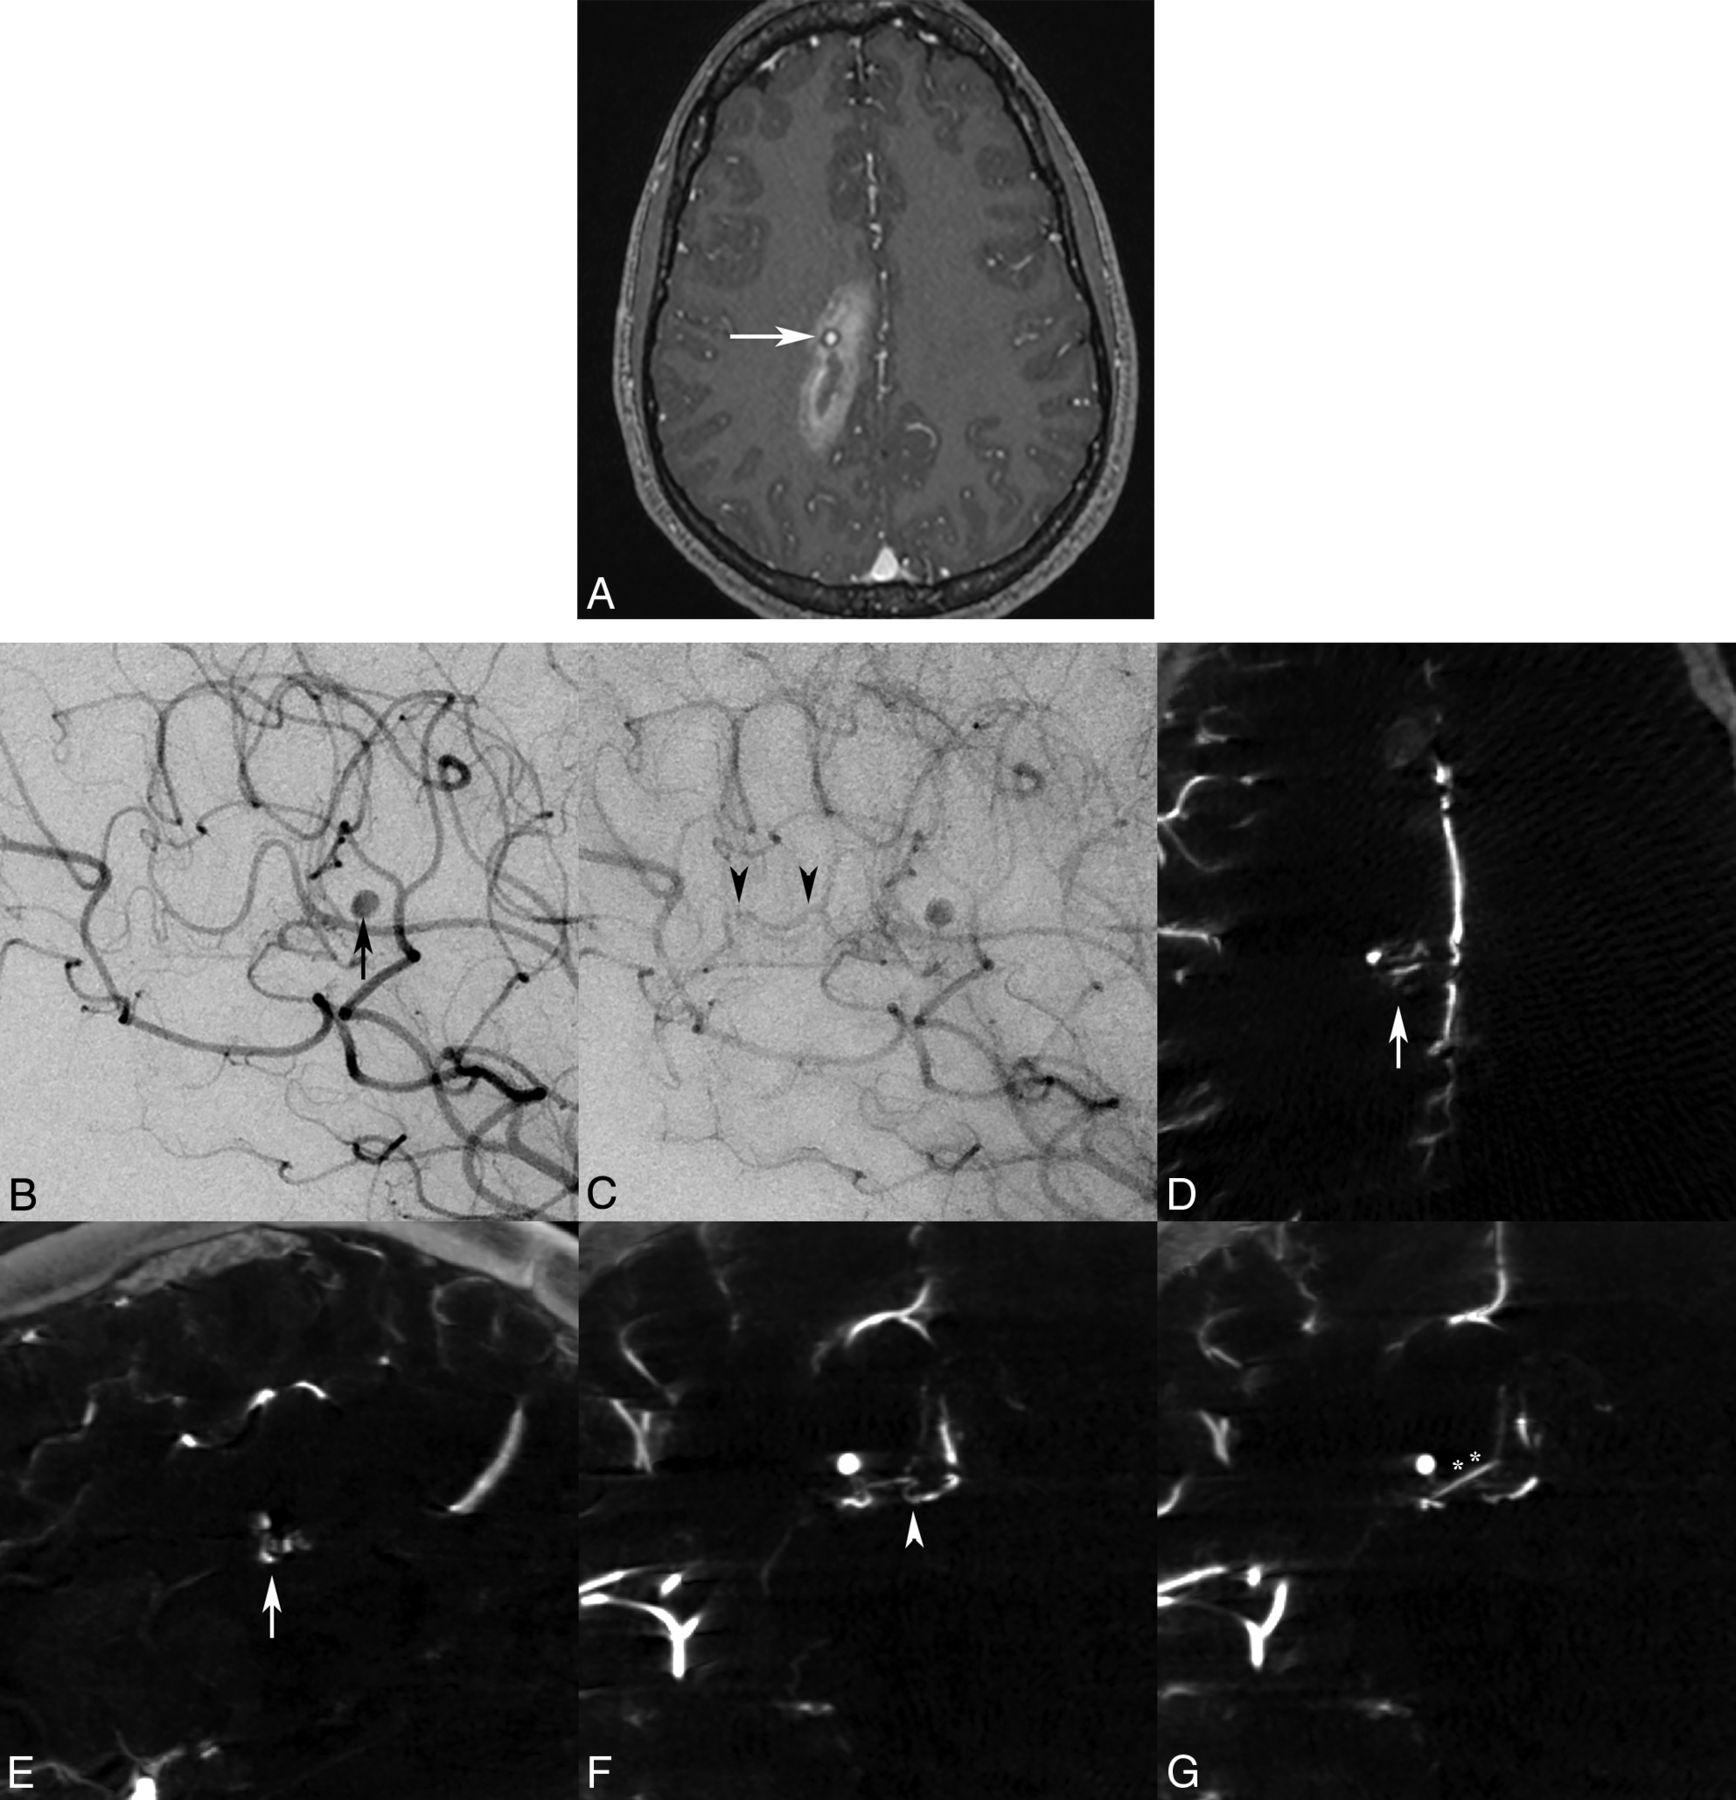

A 21-year-old woman presented to our institution with sudden headache and dizziness for 1 hour. Initial CT/CTA and MR imaging/MRA brain studies revealed an acute paramedian right frontoparietal intracerebral hemorrhage and a distal pericallosal aneurysm with suspicion of an underlying occult vascular malformation, but no abnormal vascular flow voids or nidus was seen (Fig 2A). Subsequent DSA with the 3DRA/IA-CBCTA technique was performed 2 days later confirming a 2-mm pericallosal-splenial artery aneurysm/pseudoaneurysm with suggestion of an early draining vein (Fig 2B, C), but a definitive arterial feeder and <5-mm nidus were only visualized on IA-CBCTA multiplanar reconstructions to confirm the diagnosis of a micro-AVM (Fig 2D–G).

Axial MR imaging MPRAGE postgadolinium (A) image demonstrates a right parasagittal frontoparietal intraparenchymal hemorrhage with a contrast-enhancing pseudoaneurysm (white arrow), consistent with the rupture site. Lateral oblique DSA images in the early arterial phase confirm a pericallosal anterior cerebral artery aneurysm/pseudoaneurysm (B, black arrow), with a subtle early draining vein in the capillary phase (C, black arrowheads), but no distinct vascular nidus was identified by either observer. Only IA-CBCTA multiplanar reconstructions clearly delineate a <5-mm micronidus on axial and sagittal reconstructions (D and E, white arrows). Coronal multiplanar reconstructions also assist in identification of the small arterial feeder from the pericallosal-splenial artery branch (F, white arrowhead) and single draining vein (G, double asterisks) directly associated with the micronidus and flow-induced pseudoaneurysm.